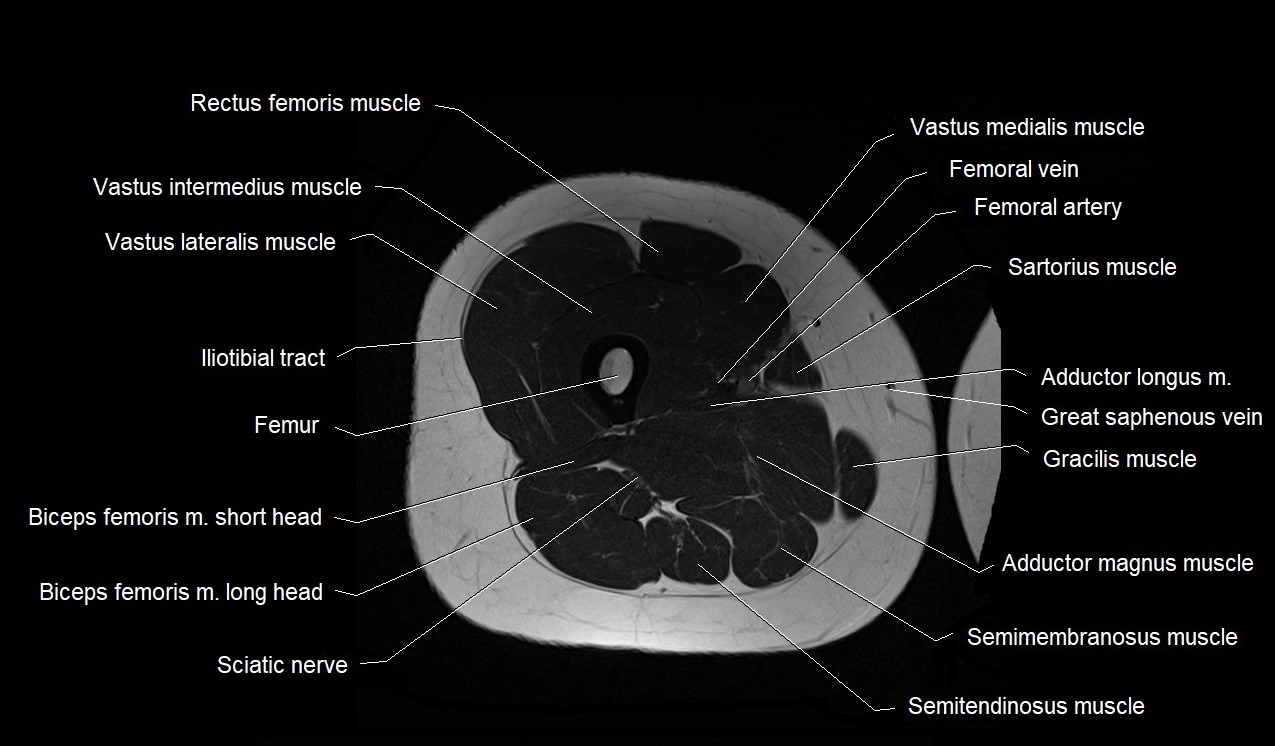

- Biceps femoris muscle (Long head)

- Biceps femoris muscle (Short head)

- Femoral artery

- Femoral vein

- Femur

- Gracilis muscle

- Iliotibial tract

- Rectus femoris muscle

- Sartorius muscle

- Semimembranosus muscle

- Semitendinosus muscle

- Vastus intermedius muscle

- Vastus lateralis muscle

- Vastus medialis muscle